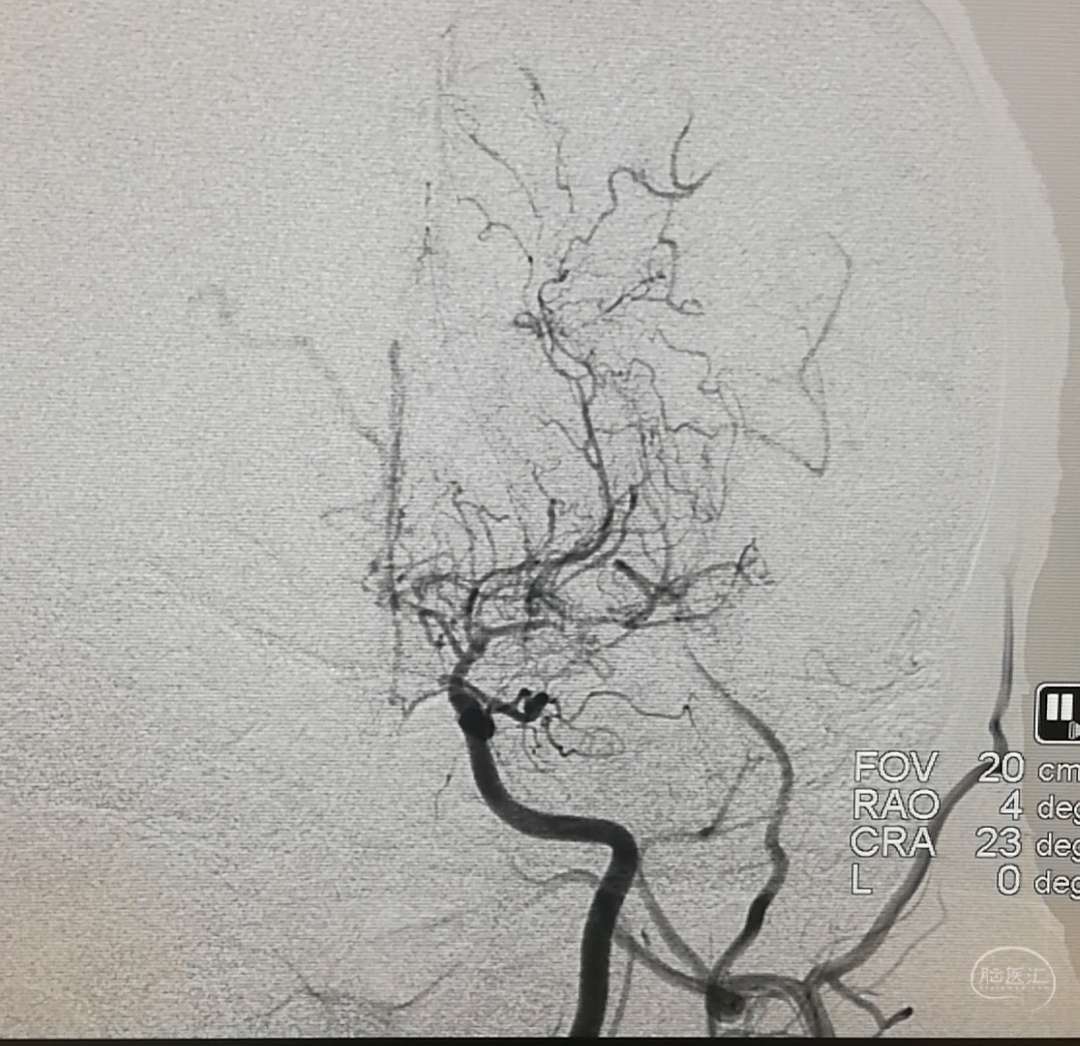

DSA示:左侧大脑中动脉闭塞,烟雾样血管形成。

DSA示颞浅A未向颅内代偿。